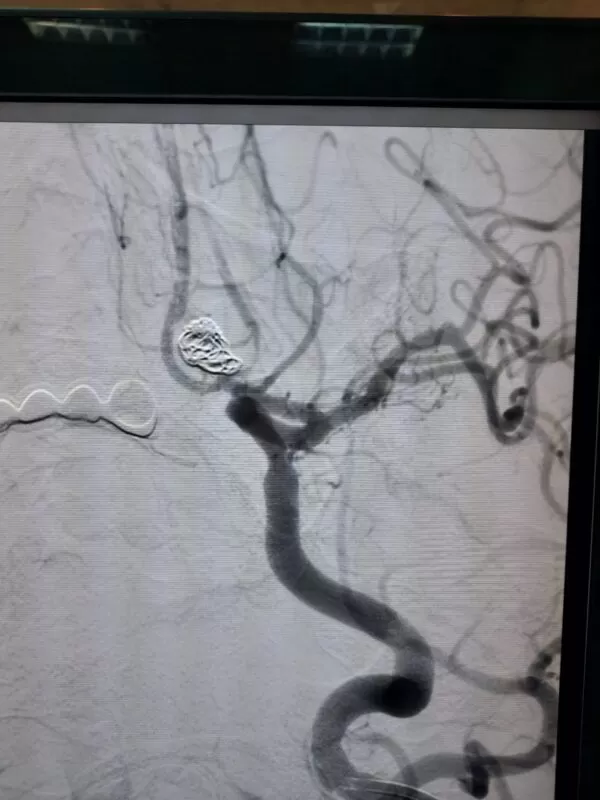

القسطرة المخية التداخلية العلاجية

يستخدم دكتور أحمد الغيطي القسطرة وهي عبارة عن أنبوبة بلاستيكية مجوفة عالية الدقة والجودة ومتناهية الصغر يتم إدخالها عبر أحد الشرايين في منطقة الفخذ وصولا إلى التمدد الشرياني.

توجد عدة طرق لعلاج التمددات الشريانية في المخ باستخدام القسطرة المخية التداخلية:

- علاج التمدد الشرياني بقيام دكتور أحمد الغيطي بوضع الملفات الحلزونية لغلق التمدد بصفة نهائية ومنع تدفق الدم خلاله لتجنب حدوث نزيف بالمخ.

- أحيانا يقوم دكتور أحمد الغيطي بعلاج التمدد الشرياني كبير الحجم باستخدام الدعامات المخية المضفرة التي تغير مسار الدم هذه الدعامات تكون عبارة عن أنابيب رفيعة لديها فتحات ضيقق للغاية لا تسمح بمرور الدم من خلالها وبالتالي لايصل إلى التمدد الشرياني أو استخدام القسطرة البالونية ذات المرونة العالية لغلق الشريان المغذي للتمدد.